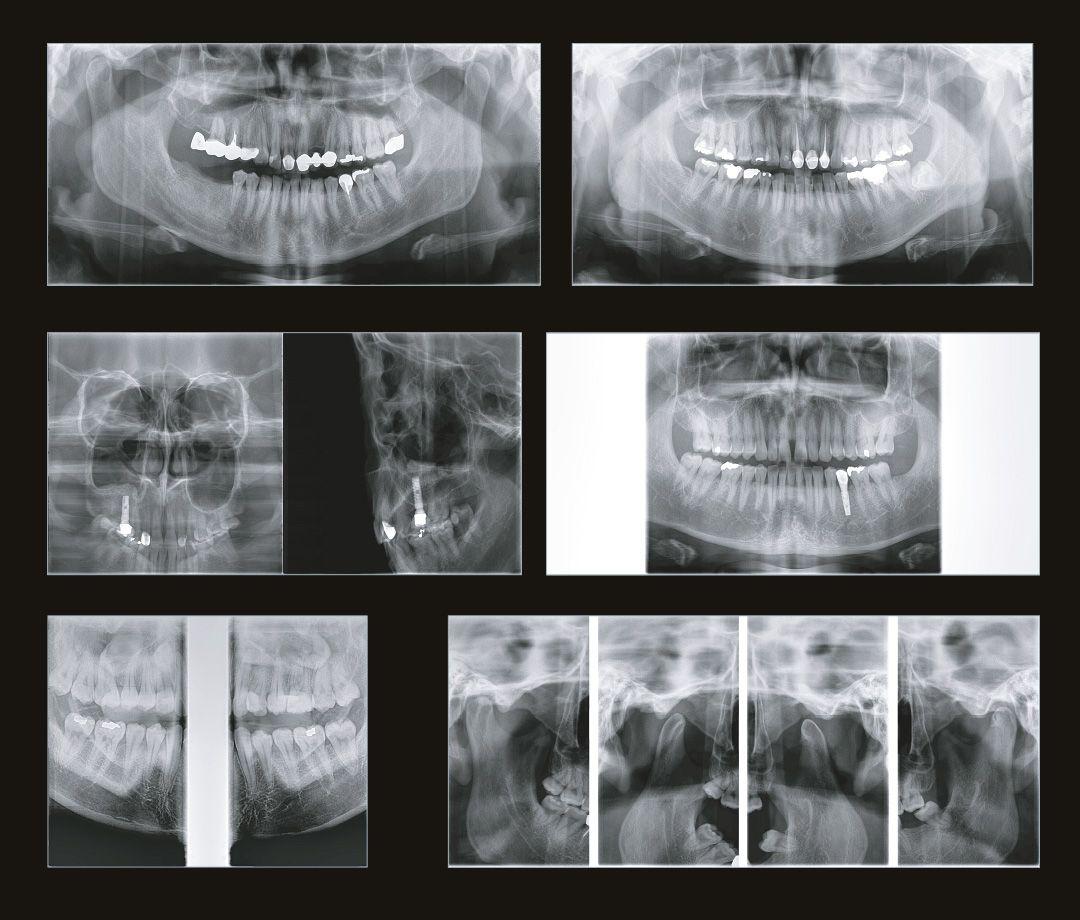

Размеры исследований дентального компьютерного 3D томографа Genoray Volux 55.jpg

Пример 3D исследования дентального компьютерного 3D томографа Volux 55 Genoray.jpg